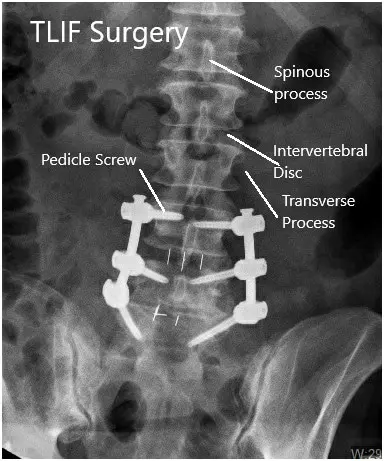

Postoperative X-ray in AP and Lateral views

Postoperative X-ray in AP and Lateral views 2

Postoperative X-ray in AP and Lateral views.